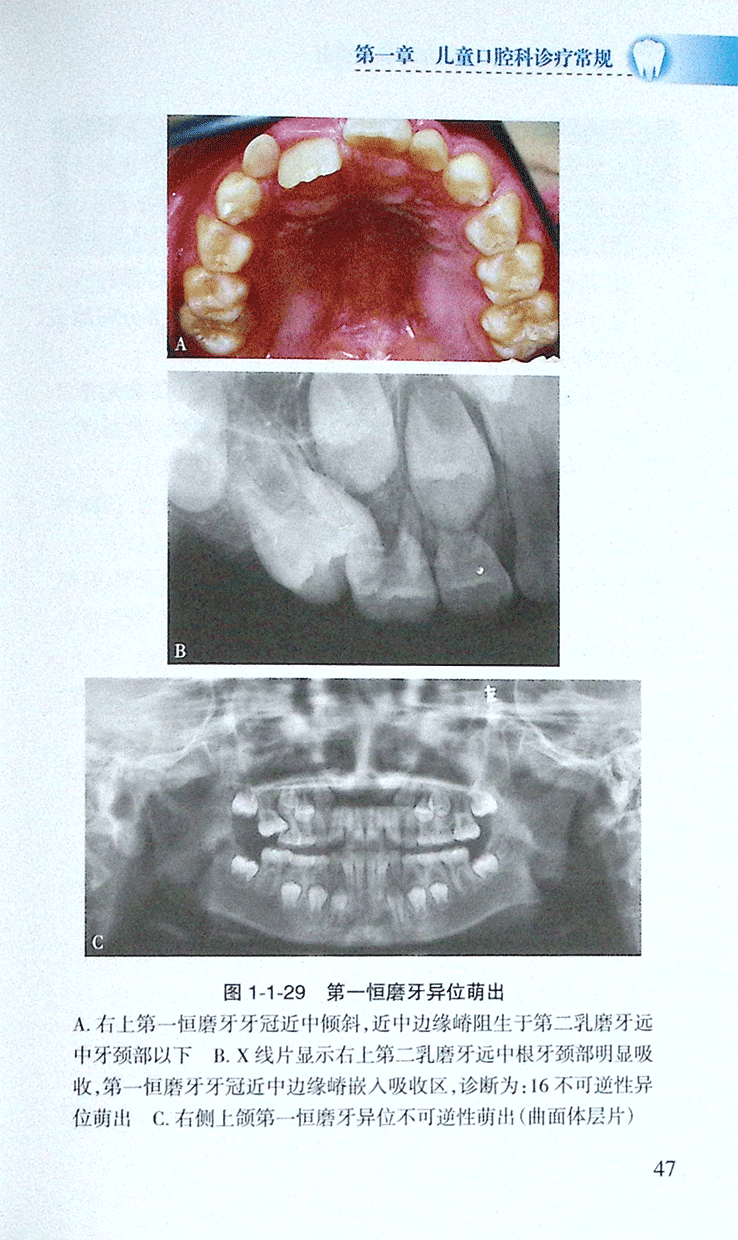

>>(六)第一恒磨牙异位萌出